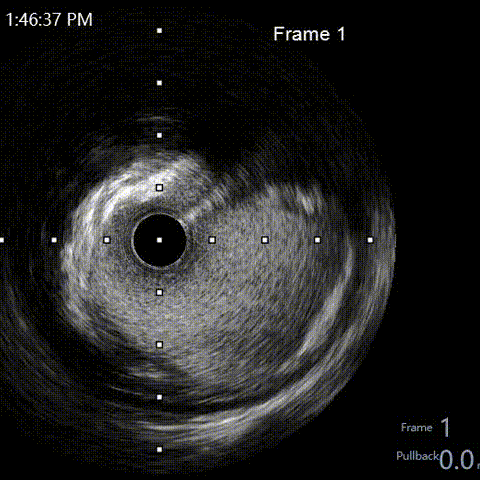

LAD pre-IVUS check RUN 1 looking for entry point

LAD pre-IVUS check RUN 2

LAD post-IVUS check RUN 3